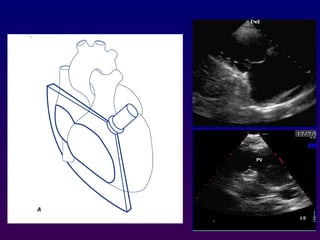

Subcostal four-chamber

The subcostal views may be obtained either with the

patient in supine position with the knees bent to

relax the abdominal musculature. The transducer is

positioned immediately below or to the right of the

xiphoid process. This allows visualization of the

basal, mid, and apical right ventricle, the inferior

interventricular septum, and anterolateral left

ventricular walls. The interatrial septum is oriented

nearly perpendicular to the ultrasound beam.

Medial rotation of the

transducer results in

imaging of the hepatic

veins and inferior vena

cava as it enters the

right atrium .Further

angulation and posterior

direction allows imaging

of the abdominal aorta

Subcostal short axis

In cases in which parasternal views are inadequate,

rotation of the probe inferiorly from the subcostal

four-chamber orientation will sometimes permit a

subcostal short-axis view at the base and mid-

ventricle. The anatomy depicted is similar to that

described for the parasternal orientation